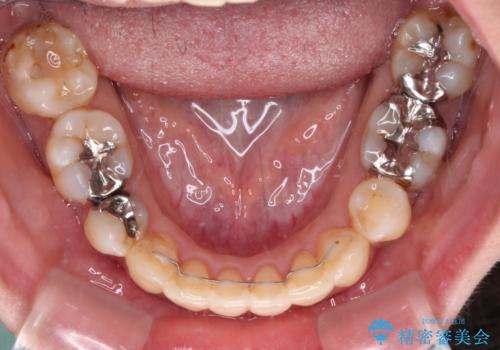

後戻りで突出した前歯をインビザラインで解消

- 抜歯矯正の後戻りで前歯が突出してきていることを気にして来院された患者様です。

口元の突出感を改善するにあたり、抜歯矯正は行うことができないため、奥歯の後方移動とIPR(歯と歯の間を削る)により達成することとしました。

再度後戻りしたときに対応しやすいよう、インビザラインにて矯正治療を行うこととしました。

舌の突出癖がなかなか改善できず、IPRによる前歯の隙間が閉じきらずに、予定よりも長い治療期間となりました。